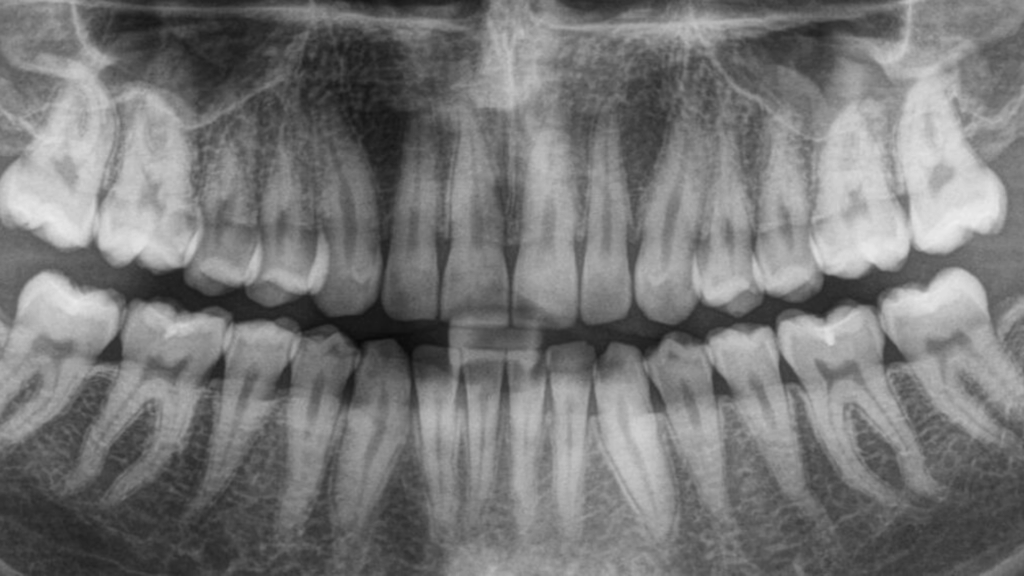

Why Lawrenceville Patients Ask About Digital Dental X-Rays Many Lawrenceville and Gwinnett County patients are more health-conscious than ever. When a dentist recommends X-rays, it’s natural to wonder about radiation exposure, safety, and whether digital dental X-rays are truly better than older methods. These concerns are especially common among parents, pregnant patients, and anyone who … Continued